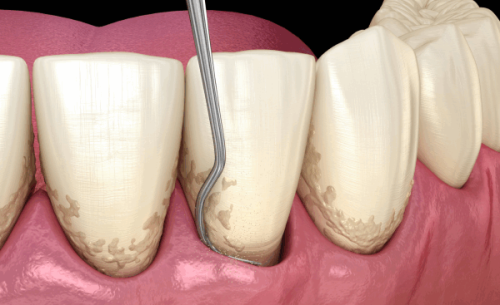

4. 种植牙周联合治疗:牛医生不仅擅长种植牙技术,还精通牙周治疗。他能够综合考虑患者的牙周状况和种植需求,制定个性化的治疗方案。在种植前后,他会对患者的牙周进行系统的治疗,确保种植体周围的牙周组织健康,提高种植的成功几率和稳定性。